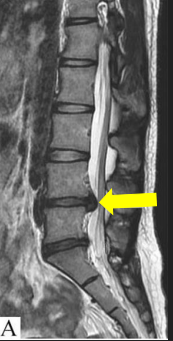

Herniated Nucleus Pulposus

aka Slipped Disk. Soft inner part of the intervertebral disk protrudes through the fibrous outer layer, pressing on the spinal cord or nerves

HNP is usually caused by ___.

Improper lifting

HNP most frequently occurs at vertebral level ___, causing ___.

L4/5

Sciatica

Which modalities are best in evaluating HNP?

CT/MRI